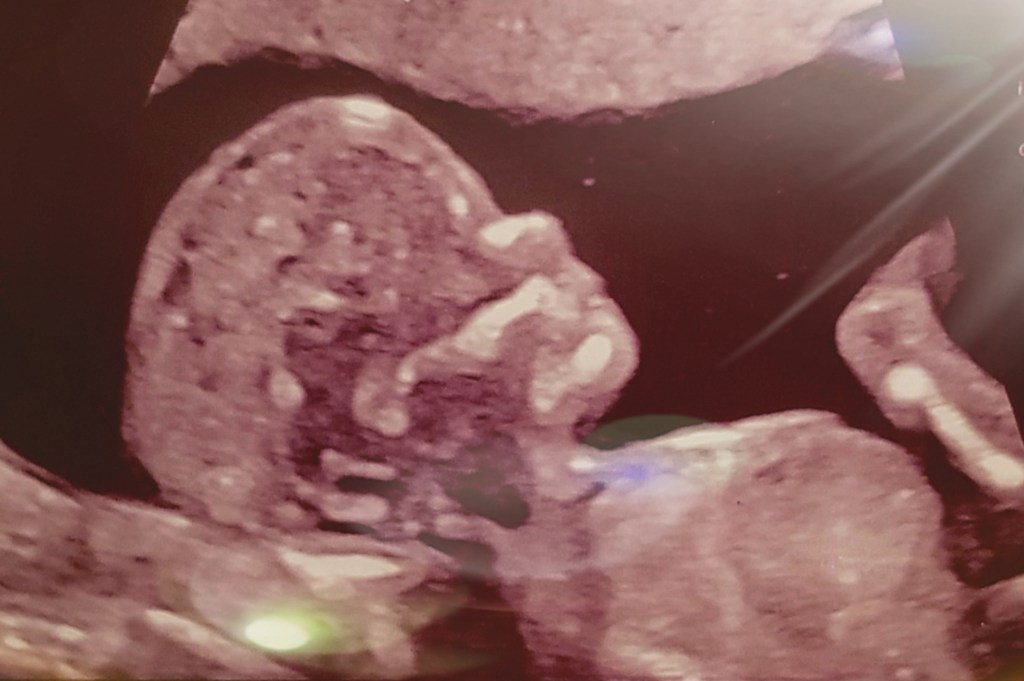

Om 8:30 uur nemen we plaats in de wachtkamer in het LUMC, waar gelukkig verder niemand anders zit. Het is ongelofelijk confronterend dat deze afdeling aan het einde van de gang van de fertiliteitsafdeling zit. We worden gelukkig snel opgehaald door een jonge, vrouwelijke echoscopiste, die eerst wat gegevens met ons doorneemt. Hierna vertelt ze over de ontwikkeling van de NIPT en de daarmee groeiende betrouwbaarheid. Volgens haar is er slecht 2% kans dat de NIPT er naast zit. De moed zakt me nog dieper in mijn schoenen en ik breek, bijna, maar houd mezelf groot. Tijdens het maken van de gespecialiseerde echo zien wíj niets anders dan een bewegelijke baby. De echoscopiste doorloopt het lichaam van ons kleine meisje van top tot teen: de hersentjes zien er normaal uit, veel andere organen ook, haar hartje klopt prachtig en haar nekplooi wijkt niet af. Stiekem houdt de hoop mij nog altijd overeind.

De echoscopiste blijft hangen bij het hartje, ze legt uit dat het hartje met deze termijn ongeveer zo klein is als een vingerkootje en doordat ons meisje zoveel beweegt, ze het erg moeilijk in beeld krijgt. Maar ook met deze onduidelijke beelden lijkt het er op dat er verschillende afwijkingen in haar ieniemini hartje te zien zijn. En er zijn nog wat dingen die de echoscopiste met haar collega wil bespreken. ‘Lijkt’ en ‘Ik moet het even met mijn collega’s bespreken’. Daar zitten we dan… En we weten nog helemaal niks.

Vrij snel worden we geroepen door een oudere, manlijke gynaecoloog. In de behandelkamer zijn nog drie mensen aanwezig. Ons wordt gevraagd of we er bezwaar tegen hebben dat een Belgische studente de echo maakt, onder begeleiding van de echoscopiste die er vorige week ook was. Het maakt ons allebei niets uit, we hebben geen idee wat er allemaal op ons af komt. De echoscopiste begint en eindelijk zien we je weer: de bewegelijke baby waar we ons zo enorm veel zorgen om maken. We houden elkaars hand vast en ik kijk bewust niet naar de materialen die ondertussen worden klaargelegd. De gynaecoloog geeft ontzettend kalm en kundig uitleg over wat hij gaat doen en hoe de punctie kan voelen. Ondertussen kijk ik naar jou en bedenk ik me hoe het in hemelsnaam kan dat we momenteel in deze vreselijke nachtmerrie zijn beland. De punctie wordt uitgevoerd, ik voel een prik door mijn huid, gevolgd door een diepere prik, zoals de gynaecoloog al omschreven had. Lichamelijk niet zo spannend, geestelijk is het hartverscheurend om te zien hoe jij naast die scherpe naald nog heerlijk ligt te spartelen.

Wanneer we worden opgehaald, hoop ik alleen maar dat ik hier geen zwangere of net bevallen vrouwen tegen kom. Gelukkig is de eerste deur direct onze kamer. De verpleegkundige geeft wat praktische uitleg en vertelt ons kort wat er ongeveer komen gaat. Ze laat papa zien waar hij koffie kan halen, bij de beschuitjesbar, een hele dubbele plek om vandaag te zijn. Wanneer de arts komt, wordt ons verzoek om een laatste echo ingewilligd. De tranen vloeien. Weer of nog steeds, ik weet het niet meer. Er lijkt geen eind aan dit tranendal te komen. Het is hartverscheurend om te beseffen dat dit écht de laatste keer is dat we je in leven zullen zien.